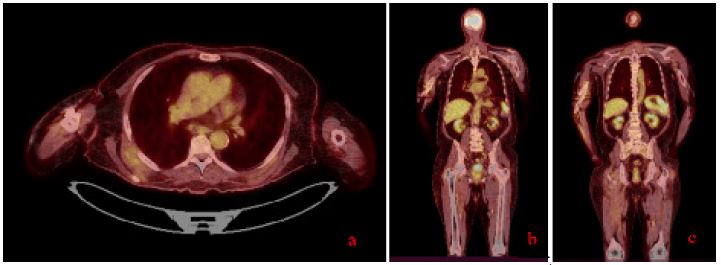

To comprehensively assess the patient’s condition, a PET-CT scan was performed (september 2024). This imaging modality revealed an additional suspicious mass in the pancreas, which had not been identified on prior imaging studies.

Figure 1: (A-C) Different sections of the patient’s PET CT scan showing an extensive, intensely hypermetabolic tissue lesion in the pancreatic head, along with a large, intensely hypermetabolic skeletal muscle lesion on the right side, with associated humeral involvement.